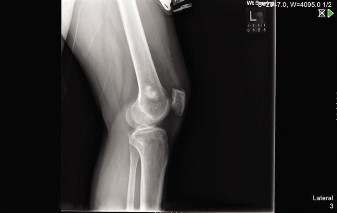

Differentiating enchondroma from low-grade chondrosarcoma in the proximal humerus involves assessing progressive pain, clinical findings, and detailed imaging. Key diagnostic indicators on X-ray and CT include chondroid matrix calcifications and the depth of endosteal scalloping. Significant scalloping (e.g., 3-4mm) with persistent pain strongly suggests potential for low-grade chondrosarcoma.

Asymptomatic lesions with classic "rings and arcs" or "popcorn" calcifications, without significant endosteal scalloping or periosteal reaction, are highly indicative of enchondroma and warrant serial observation. Conversely, lesions demonstrating deep scalloping, cortical breakthrough, soft tissue extension, or progressive enlargement require surgical intervention.

Thorough preoperative planning relies heavily on advanced imaging modalities. Plain radiographs in orthogonal planes are the initial step, assessing for the classic chondroid matrix mineralization. Computed Tomography provides superior resolution of cortical integrity, accurately quantifying the depth of endosteal scalloping and identifying subtle cortical breaches.